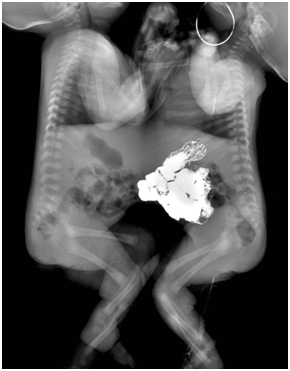

Imaging

The twins were joined from the lower chest to the umbilicus area. There was no bony connection on conventional x-rays. The hearts and lungs were visible above the conjoined diaphragm. The left- and right-side twins were called Twin A and Twin B, respectively. Barium sulfate was given to Twin A via a nasogastric tube. Serial images showed no evidence of digestive tract communication, and only loops of the upper small bowel of Twin A were seen to project into the abdominal cavity of Twin B through an abdominal wall defect (Figure 1). US showed that the livers of the twins were fused, and the gallbladder and portal vein of Twin B were clearly seen, while those of Twin A were invisible due to intestinal gas interference (not shown). Based on the echo findings, a CT study was designed.

Figure 1 For barium studies, the baby on the right side was given barium sulfate. Barium sulfate was observed only in the intestines of one baby, and no evidence of digestive tract communication was seen.